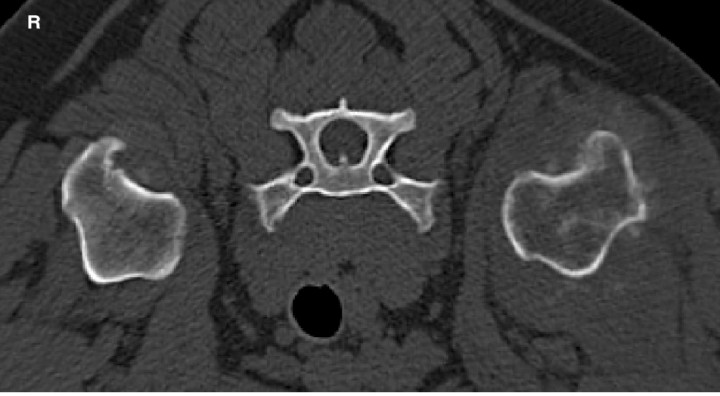

Skeletal system

Primary bone tumors, of which the osteosarcoma is the most common in dogs, are usually assessed with radiographs, showing varying degree of osteolysis, periosteal reaction, cortical destruction and transition zone length (Fig. 9).[ Thrall DE. Radiographic features of bone tumors and bone infections. En Thrall DE (ed): Textbook of Veterinary Diagnostic Radiology, St Louis, Missouri, Elsevier, 2013; 307-317. ]

<p>8 year-old German Shepherd Dog with a primary bone tumour at the level CT transverse image of the metaphysis of the left humerus in bone window showing a mixed productive and osteolytic aggressive bone lesion with multifocal cortical destruction. R: right.</p>

Figura 9

8 year-old German Shepherd Dog with a primary bone tumour at the level CT transverse image of the metaphysis of the left humerus in bone window showing a mixed productive and osteolytic aggressive bone lesion with multifocal cortical destruction. R: right.

In terms of treatment options, limb amputation is commonly performed, although may not be chosen due to concomitant orthopaedic disease, owner compliance or neurologic disease. In case of limb-sparing surgery, determining lesion margins is essential. Various modalities including radiographs, non-contrast CT, MRI and scintigraphy have been reported with a tendency to overestimate lesion length.[ Wallack ST, Wisner ER, Werner JA et al.: Accuracy of magnetic resonance imaging for estimating intramedullary osteosarcoma extent in pre-operative planning of canine limb-salvage procedures. Vet Radiol Ultrasound 2002; 5:432-441. [PubMed] ] A more recent study described multidetector CT with acquisition of submillimeter thick images to be a feasible modality. It has been shown that assessing with CT intramedullary/endosteal abnormalities represents the best predictor of tumor length.[ Karnik KS, Samii VF, Weisbrode SE et al.: Accuracy of computed tomography in determining lesion size in canine appendicular osteosarcoma. Vet Radiol Ultrasound 2012; 53:273-279. [PubMed] ]